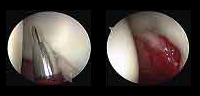

La artroscopia es un procedimiento quirúrgico que permite estudiar, diagnosticar y tratar problemas en una articulación. Consiste en la introducción por punción, en este caso dentro de la cadera, de un sistema óptico con fuente de luz conectado a una cámara digital que permite visualizar las estructuras intraarticulares. - ¿Cuáles son las lesiones más frecuentes que trata la artroscopia de cadera?

- Lesiones del rodete glenoideo o labrum acetabular

- Lesiones del cartílago articular, que rodea la cabeza del fémur, provocando irregularidades en la superficie de contacto entre fémur y acetábulo